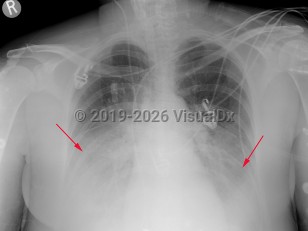

Fever, Cough, 50-59 year old Female

COVID-19